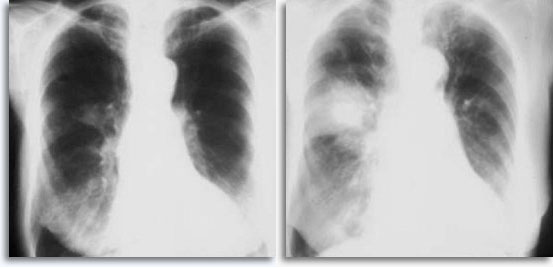

Met transthoracale percutane longaspiratie als referentiepunt, worden bloedingen verwacht als de naald door het borstvlies gaat en het longcelweefsel binnendringt. Dit is gewoonlijk zichtbaar als een versterking van de target in postpunctie borstkasfilmpjes.

|

Dit wordt soms in verband gebracht met zelf elimiteerde hemoptyse als een klinische reactie van de intraparenchymale lekkage. Pneumothoraxis een bijkomstig verschijnsel van tranthoracale aspiratiebiopsie omdat de naald het borstvlies beschadigt, terwijl deze zijn weg zoekt naar het parenchymatische doel, hetgeen kan resulteren in enige longcollaps. Dit is symptomatisch voor pneumothorax, hetgeen wordt beschouwd als een complicatie. In het algemeen moet er een buis in de borst worden ingebracht zodat de long weer met lucht kan worden gevuld.

|

|

Enkele factoren die het voorkomen van symptomatische pneumothorax beïnvloeden, zijn de leeftijd van de patiënt, de afmeting, plaats en diepte van de laesies, het aantal puncties, aanwezigheid van emfyseem, intensiteit van nauwkeurig onderzoek met postprocedurele films en de ervaring van de aspirator.